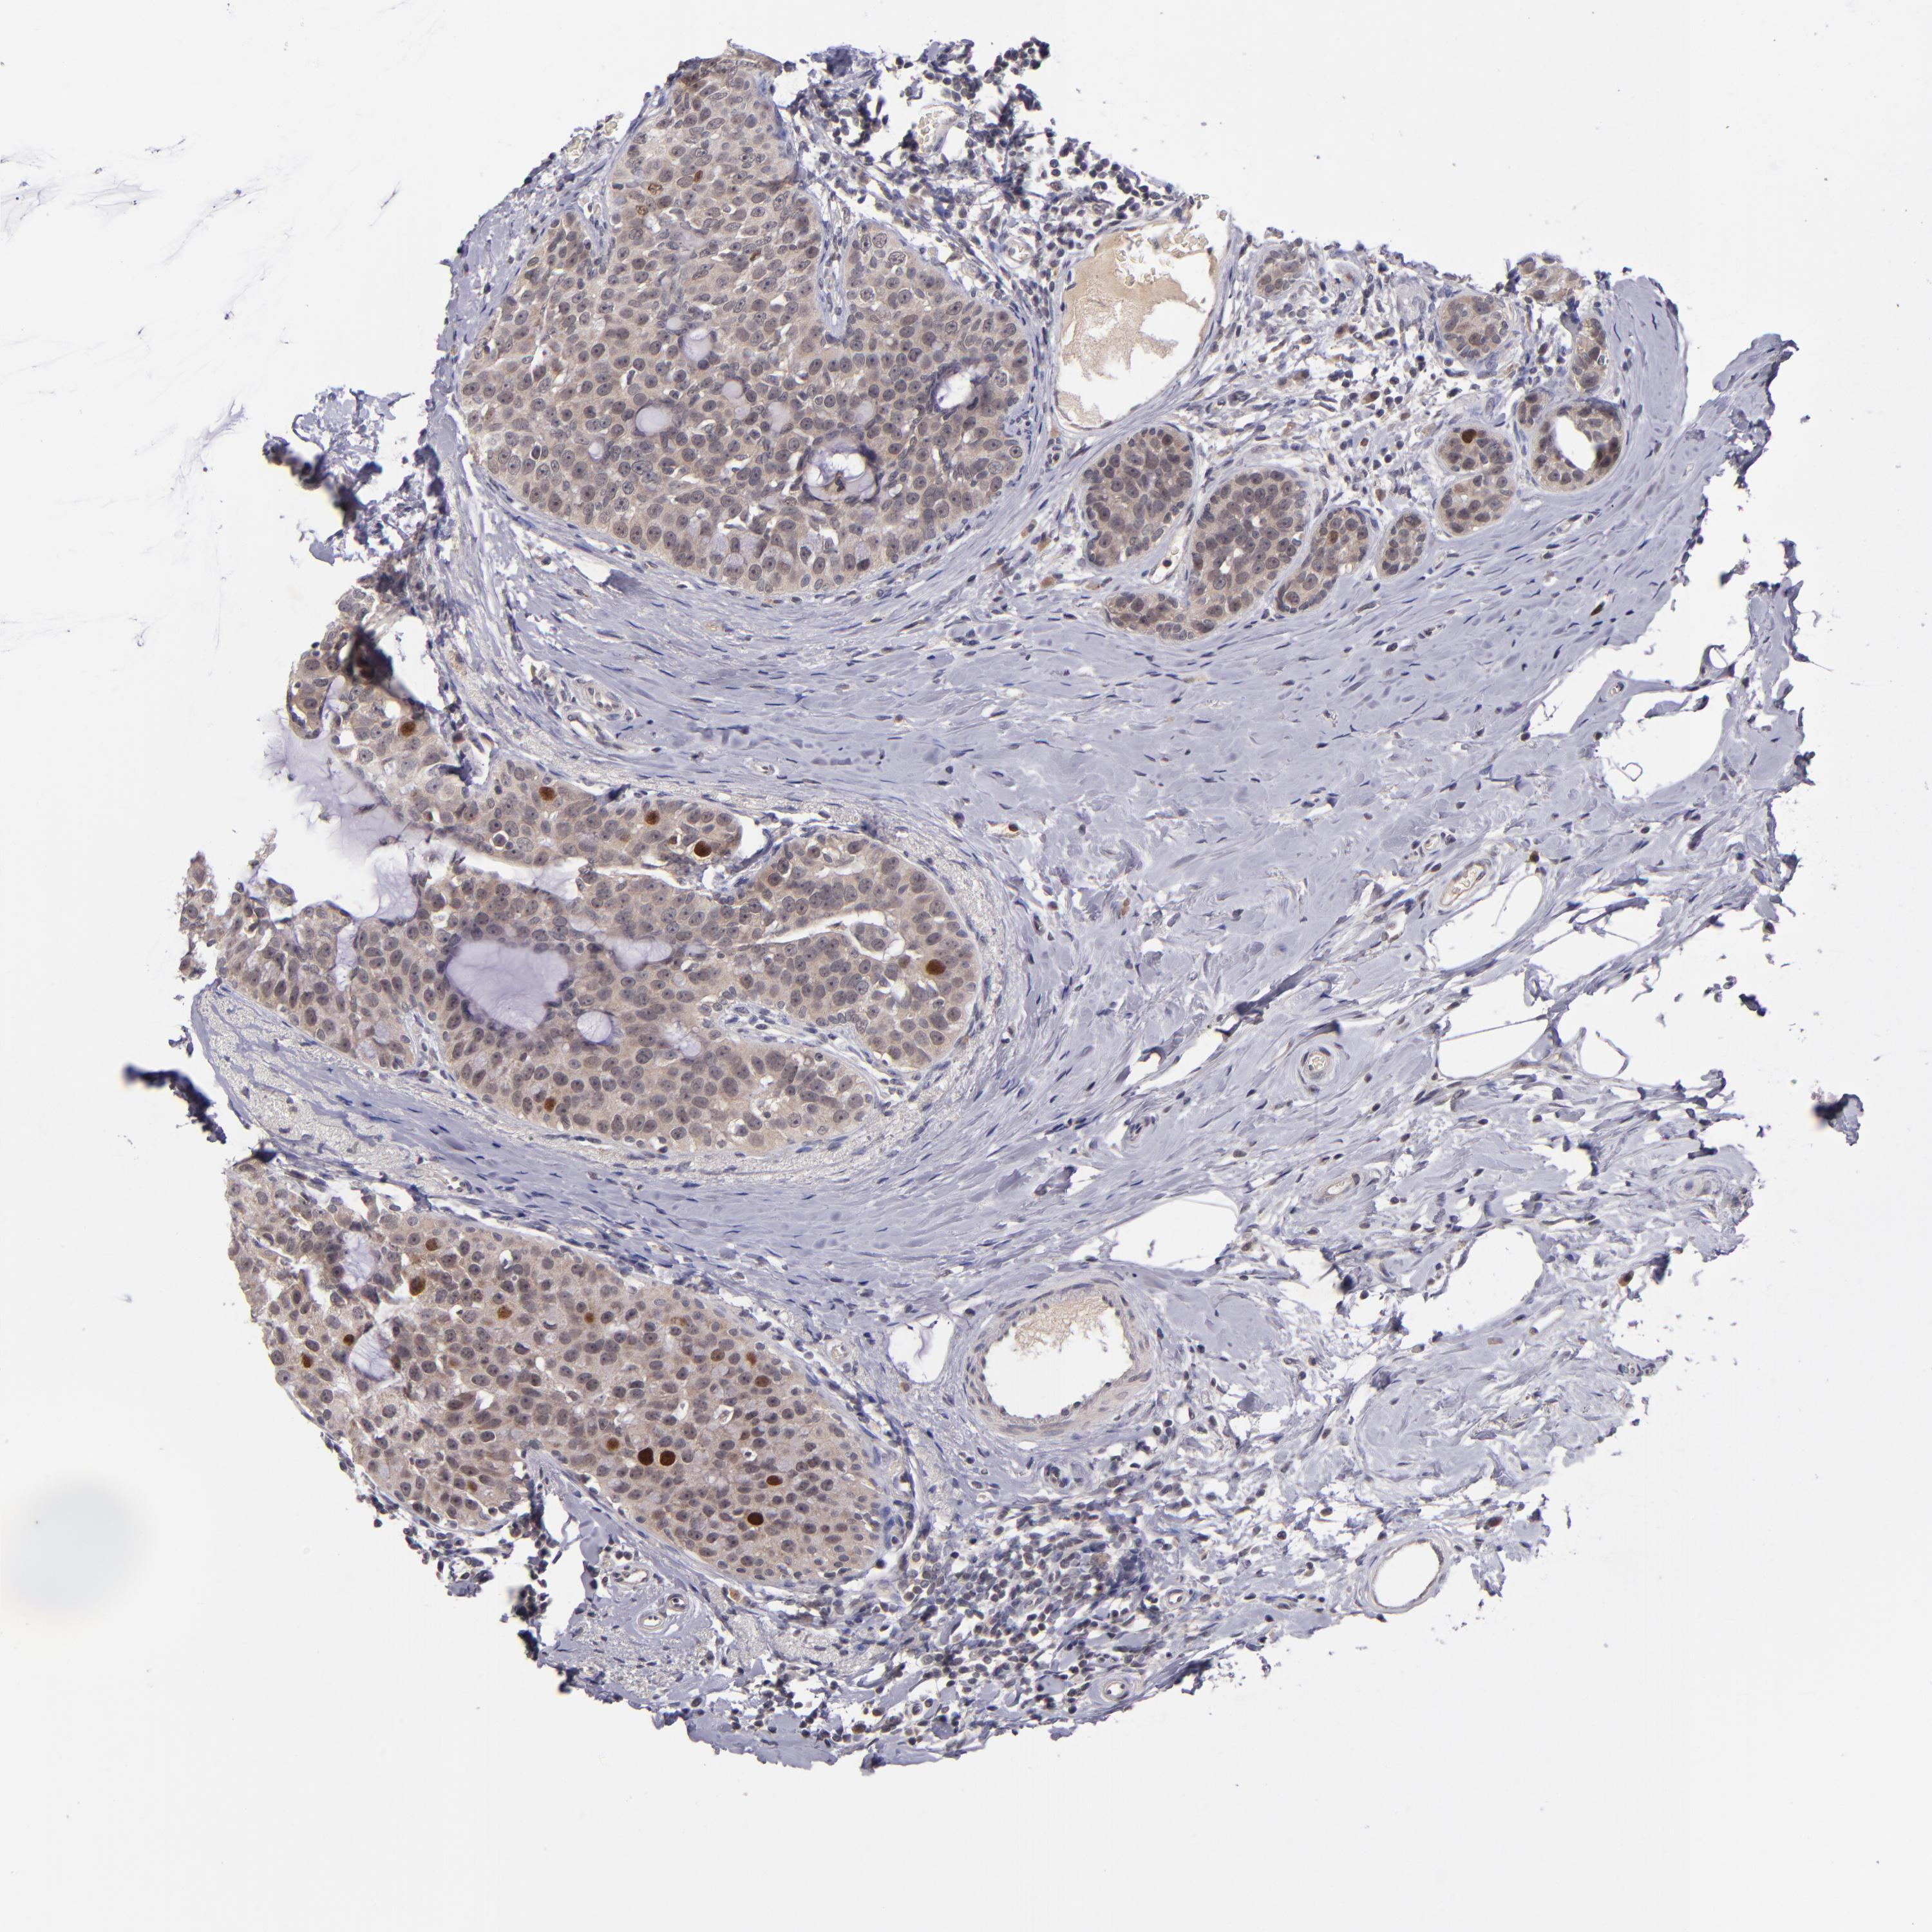

CANCER BREAST CANCER Show tissue menu

BRCA TCGA BRCA VALIDATION PROTEIN EXPRESSION

ANTIBODIES

AND

VALIDATION